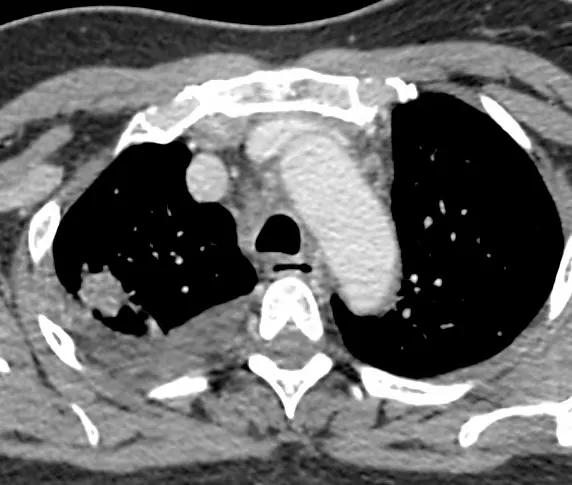

术前CT示右上肺分叶状结节伴双肺多发小结节,考虑右上肺癌伴双肺转移

术前增强,结节小,约2.0cm。